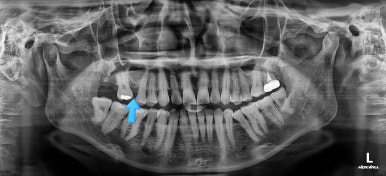

초진 때의 사진입니다.

제일 하단의 X-ray에서 문제점이 보이는데요.

해당 부분의 어금니 1개가 없었어요.

어금니가 없어진지 꽤 시간이 흘렀기 때문에 몇 가지 문제점이 나타나는데요.